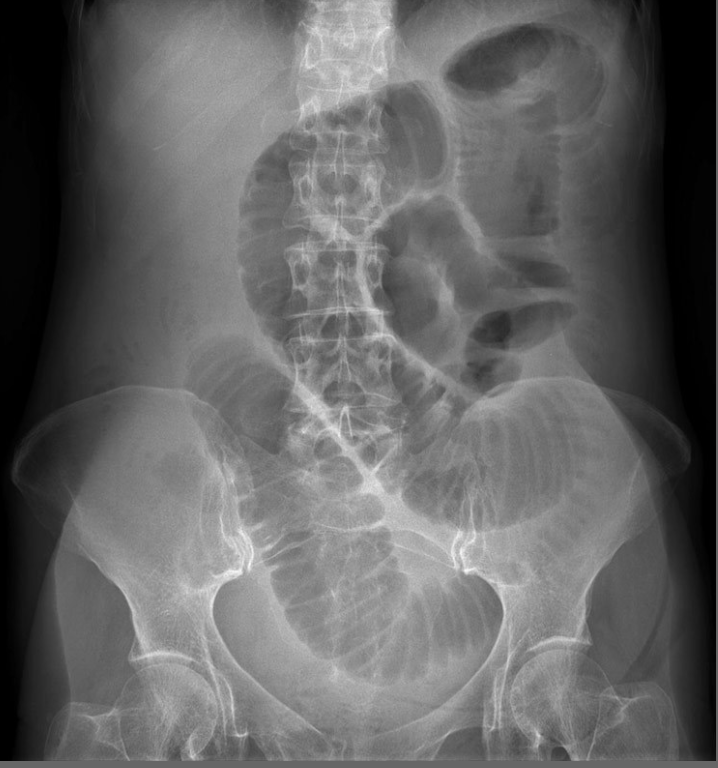

Describe what is seen in this AXR [3]

A

Small bowel obstruction - features

Centrally located multiple dilated loops of gas filled bowel (arrowheads)

Valvulae conniventes (arrow) are visible - confirming this is small bowel